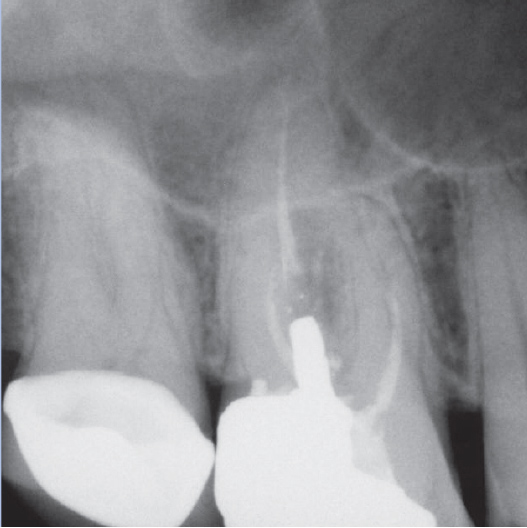

Before

After

Before Root Canal treatment

After Root Canal treatment